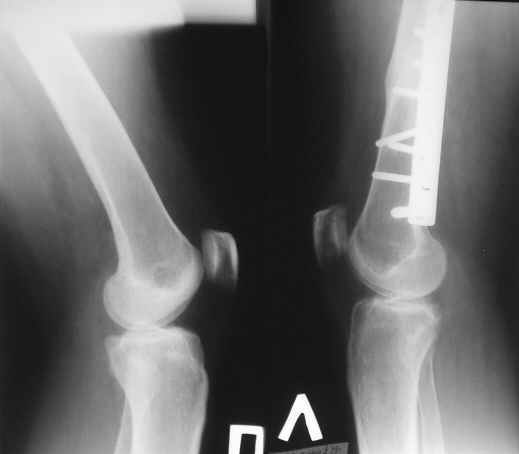

На консультацию пришла женщина, 40 лет. В 2004г. автодорожная травма - перелом бедра. Остеосинтез пластиной. Мягкие ткани зажили первичным натяжением, перелом сросся.

Укорочение бедра 0,5 см. Беспокоят постоянные боли в области колена. Снимки на руках были только вот эти.

Думаю, что оперировавшие коллеги не устранили ротационное смещение. Какие у кого соображения в отношении дальнейшей тактики?